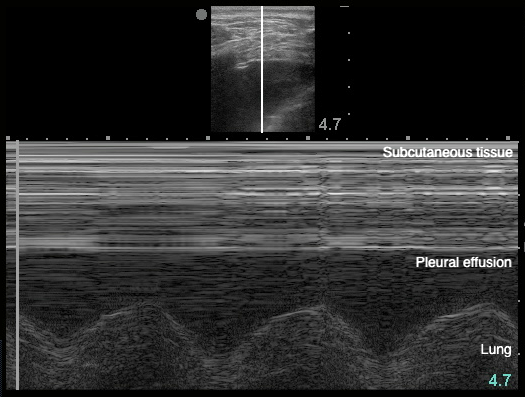

- Sinusoid sign: represents movement of lung within the effusion22

- Figure 20. Sinusoid sign

- Demonstrates fluctuating distance between visceral and parietal pleura during respiratory cycle